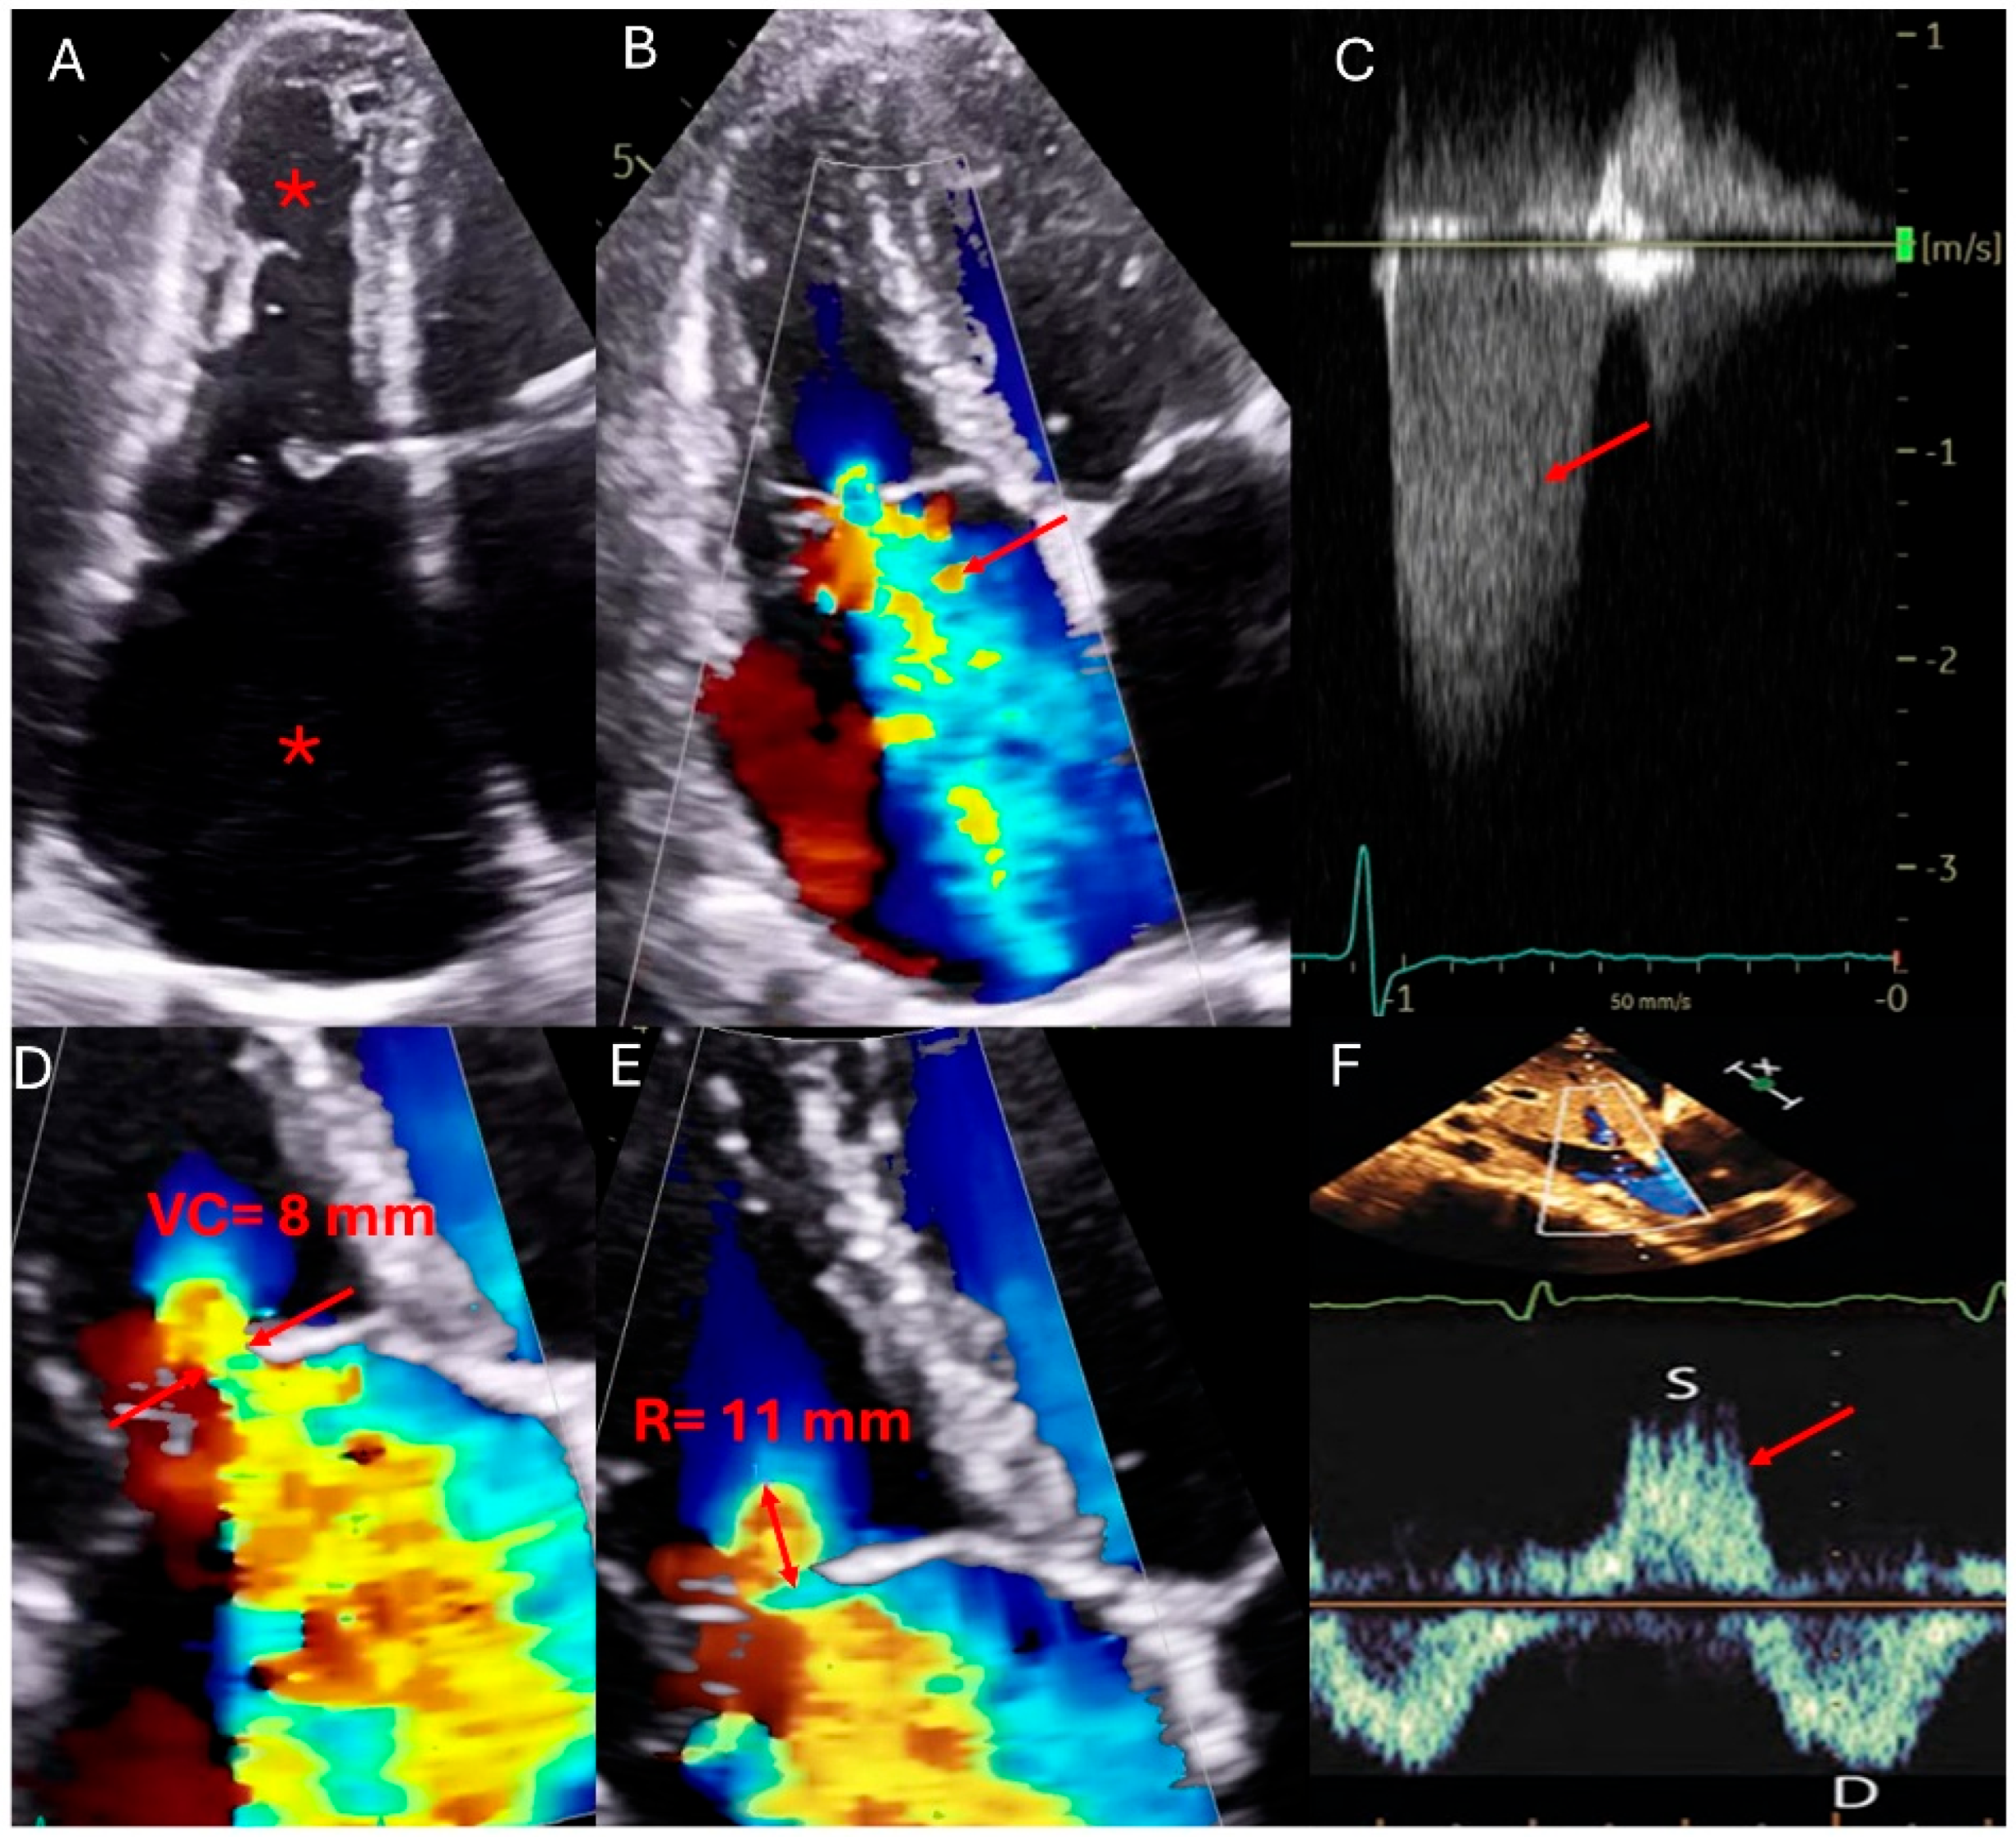

Transesophageal echocardiography (TEE) complements TTE by allowing for detailed visualization of the TV through various esophageal and gastric views. The guidelines for TEE outline a systematic approach involving multiplane angles and varying depths, from mid-esophageal to deep transgastric positions, to capture comprehensive images of the TV. This method enables the visualization of all three TV leaflets and the adjacent cardiac structures [29]. The proximity of the esophagus and stomach to the heart’s position facilitates these detailed examinations, which are particularly beneficial in 3D imaging, which offers superior resolution in the axial plane compared to lateral and elevational planes [29]. Furthermore, 3D echocardiography enhances the identification of tricuspid leaflets (number of leaflets, shapes, and presence of indentations) and related anatomical structures, providing crucial insights into the TV complex’s spatial orientation and aiding in the accurate assessment of valve pathology and function [30]. During procedures like transcatheter edge-to-edge repair, TEE offers real-time guidance, ensuring precise device placement and monitoring for potential complications (Figure 2). Additionally, post-procedural TEE helps evaluate residual regurgitation, leaflet integrity, and overall procedural success, optimizing patient outcomes [31]. Stress echocardiography, though less commonly used in TR, helps assess pulmonary hypertension and functional assessment, particularly in concomitant pulmonary conditions. Typically, TR worsens with exercise due to increased right ventricular afterload or pulmonary hypertension. In addition, stress echocardiograms can provide insights into right ventricular functional reserve and exercise-induced changes in regurgitant volume, which may guide therapeutic decisions. TEE and stress echocardiography play complementary roles in characterizing isolated TR, especially in complex cases or when the parameters are approaching indications for surgical intervention [27].

Figure 2—TEE-3D MPR showing guidance for transcatheter tricuspid clip.

Figure 2. This composite echocardiographic figure illustrates stepwise transesophageal echocardiographic (TEE) guidance for transcatheter tricuspid clip placement using 3D multiplanar reconstruction (MPR). (A) En-face 3D view of the tricuspid valve for leaflet assessment showing central coaptation gap (red arrow). (B) MPR views demonstrating tricuspid regurgitant jet severity (red arrows). (C) Mid-esophageal 0-degree view showing catheter direction through IVC directed towards the tricuspid valve. (D) Biplane imaging confirming clip orientation and leaflet approximation. (E) 3D MPR-guided leaflet grasping during clip deployment. (F) Post-deployment color Doppler showing trivial residual tricuspid regurgitation and successful leaflet coaptation using the tricuspid clip (red arrows).